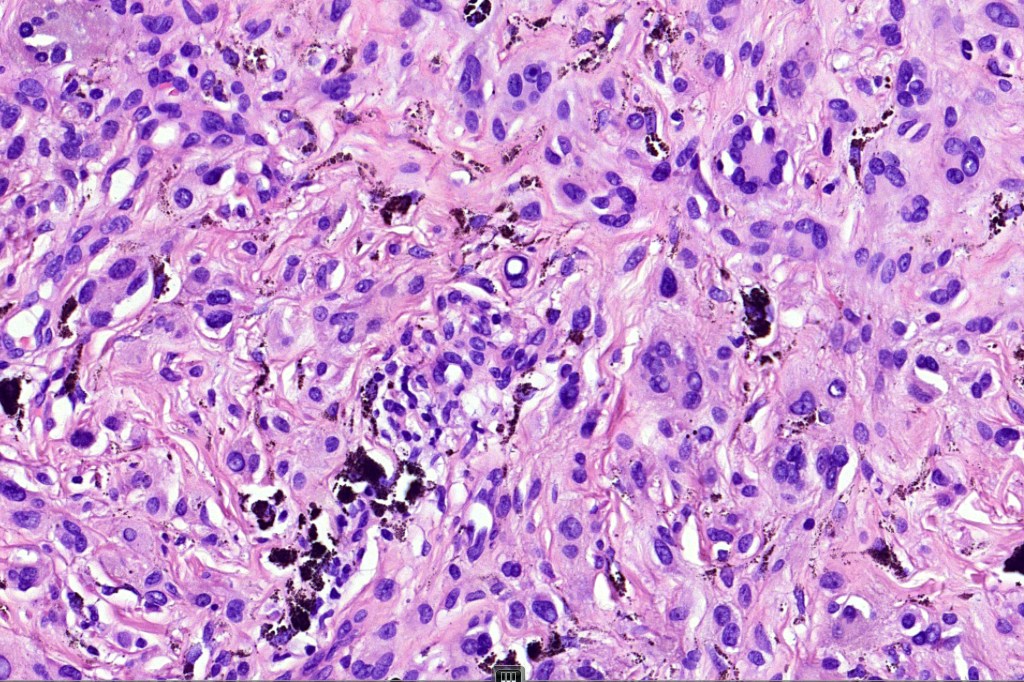

•Superficial epithelioid cells

•Deep spindle cells

•Focal atypia (enlarged, hyperchromatic nuclei)

•Clear cells

•Dendritic cells

•Melanophages

•Multinucleate giant cells

• Cytoplasmic intranuclear pseudo-inclusions, small eosinophilic nucleoli

•Occasional mitoses